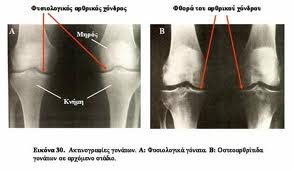

Σύμφωνα με το iator.gr ,η οστεοαρθρίτιδα χαρακτηρίζεται από την βαθμιαία φθορά του αρθρικού χόνδρου και την αντιδραστική ανάπτυξη νέου οστού με την μορφή των οστεοφύτων, δηλαδή μικρών οστέινων προεκτάσεων (τα περίφημα «άλατα»). Ο αρθρικός υμένας αντιδρά σε αυτήν κατάσταση παράγοντας περισσότερο αρθρικό υγρό με αποτέλεσμα την παρουσία οιδήματος.

Ο ορθοπεδικός ιατρός θα θέσει τη διάγνωση με βάση τα ανωτέρω και την κλινική εξέταση. Οι απλές ακτινογραφίες βοηθούν στην επιβεβαίωση της διάγνωσης καθώς διακρίνεται η μείωση του μεσοδιαστήματος μεταξύ των οστών εξαιτίας της καταστροφής των χόνδρων καθώς και η τυχόν παρουσία οστεοφύτων. Οι εξετάσεις αίματος χρησιμεύουν στον αποκλεισμό αυτοάνοσης αρθρίτιδας.